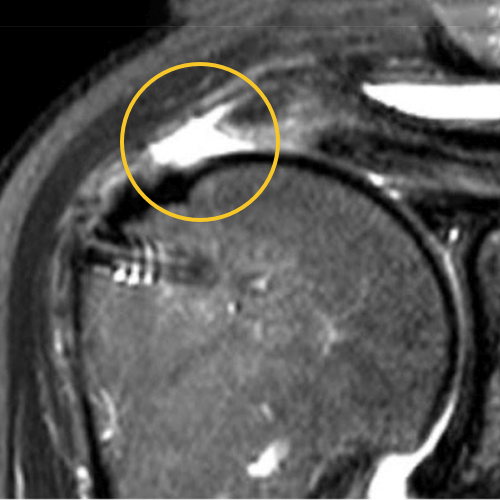

We published this case study in the JOEI (Journal of Orthopedic Experience and Innovation) Journal. We did a revision of the large type-II repair and augmented it with BioBrace®. You can see the pre-op and three-month MRI below. Still fluid in the subacromial space but that tendon is clearly coming across into the footprint. Then, an eight-month MRI shows there's no further fluid in the subacromial space and maturation of that repair across the footprint.

Pre-OP

3 Months